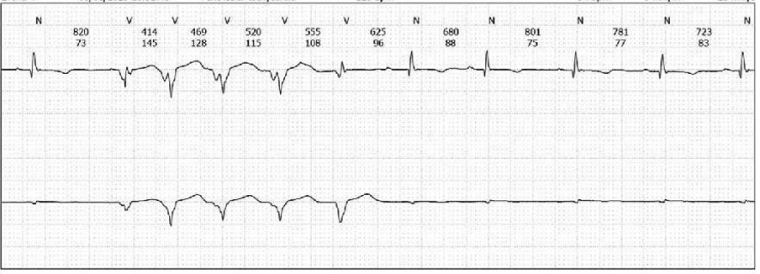

On exercise testing (figure 4), there were isolated ventricular ectopics of at least 2 different morphologies at rest and during early exercise, in isolation and in a trigeminal pattern, longest for 5 cycles, of one morphology. She developed symptoms of breathlessness at stage IV of the exercise test but no syncope or presyncope.  There were non-specific ST segment changes throughout.